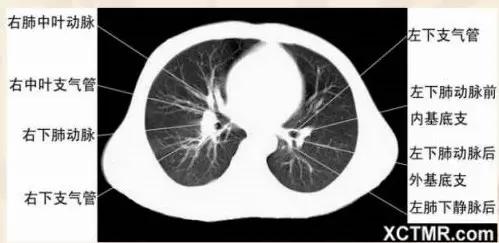

右中叶支气管层面

右基底支气管层面